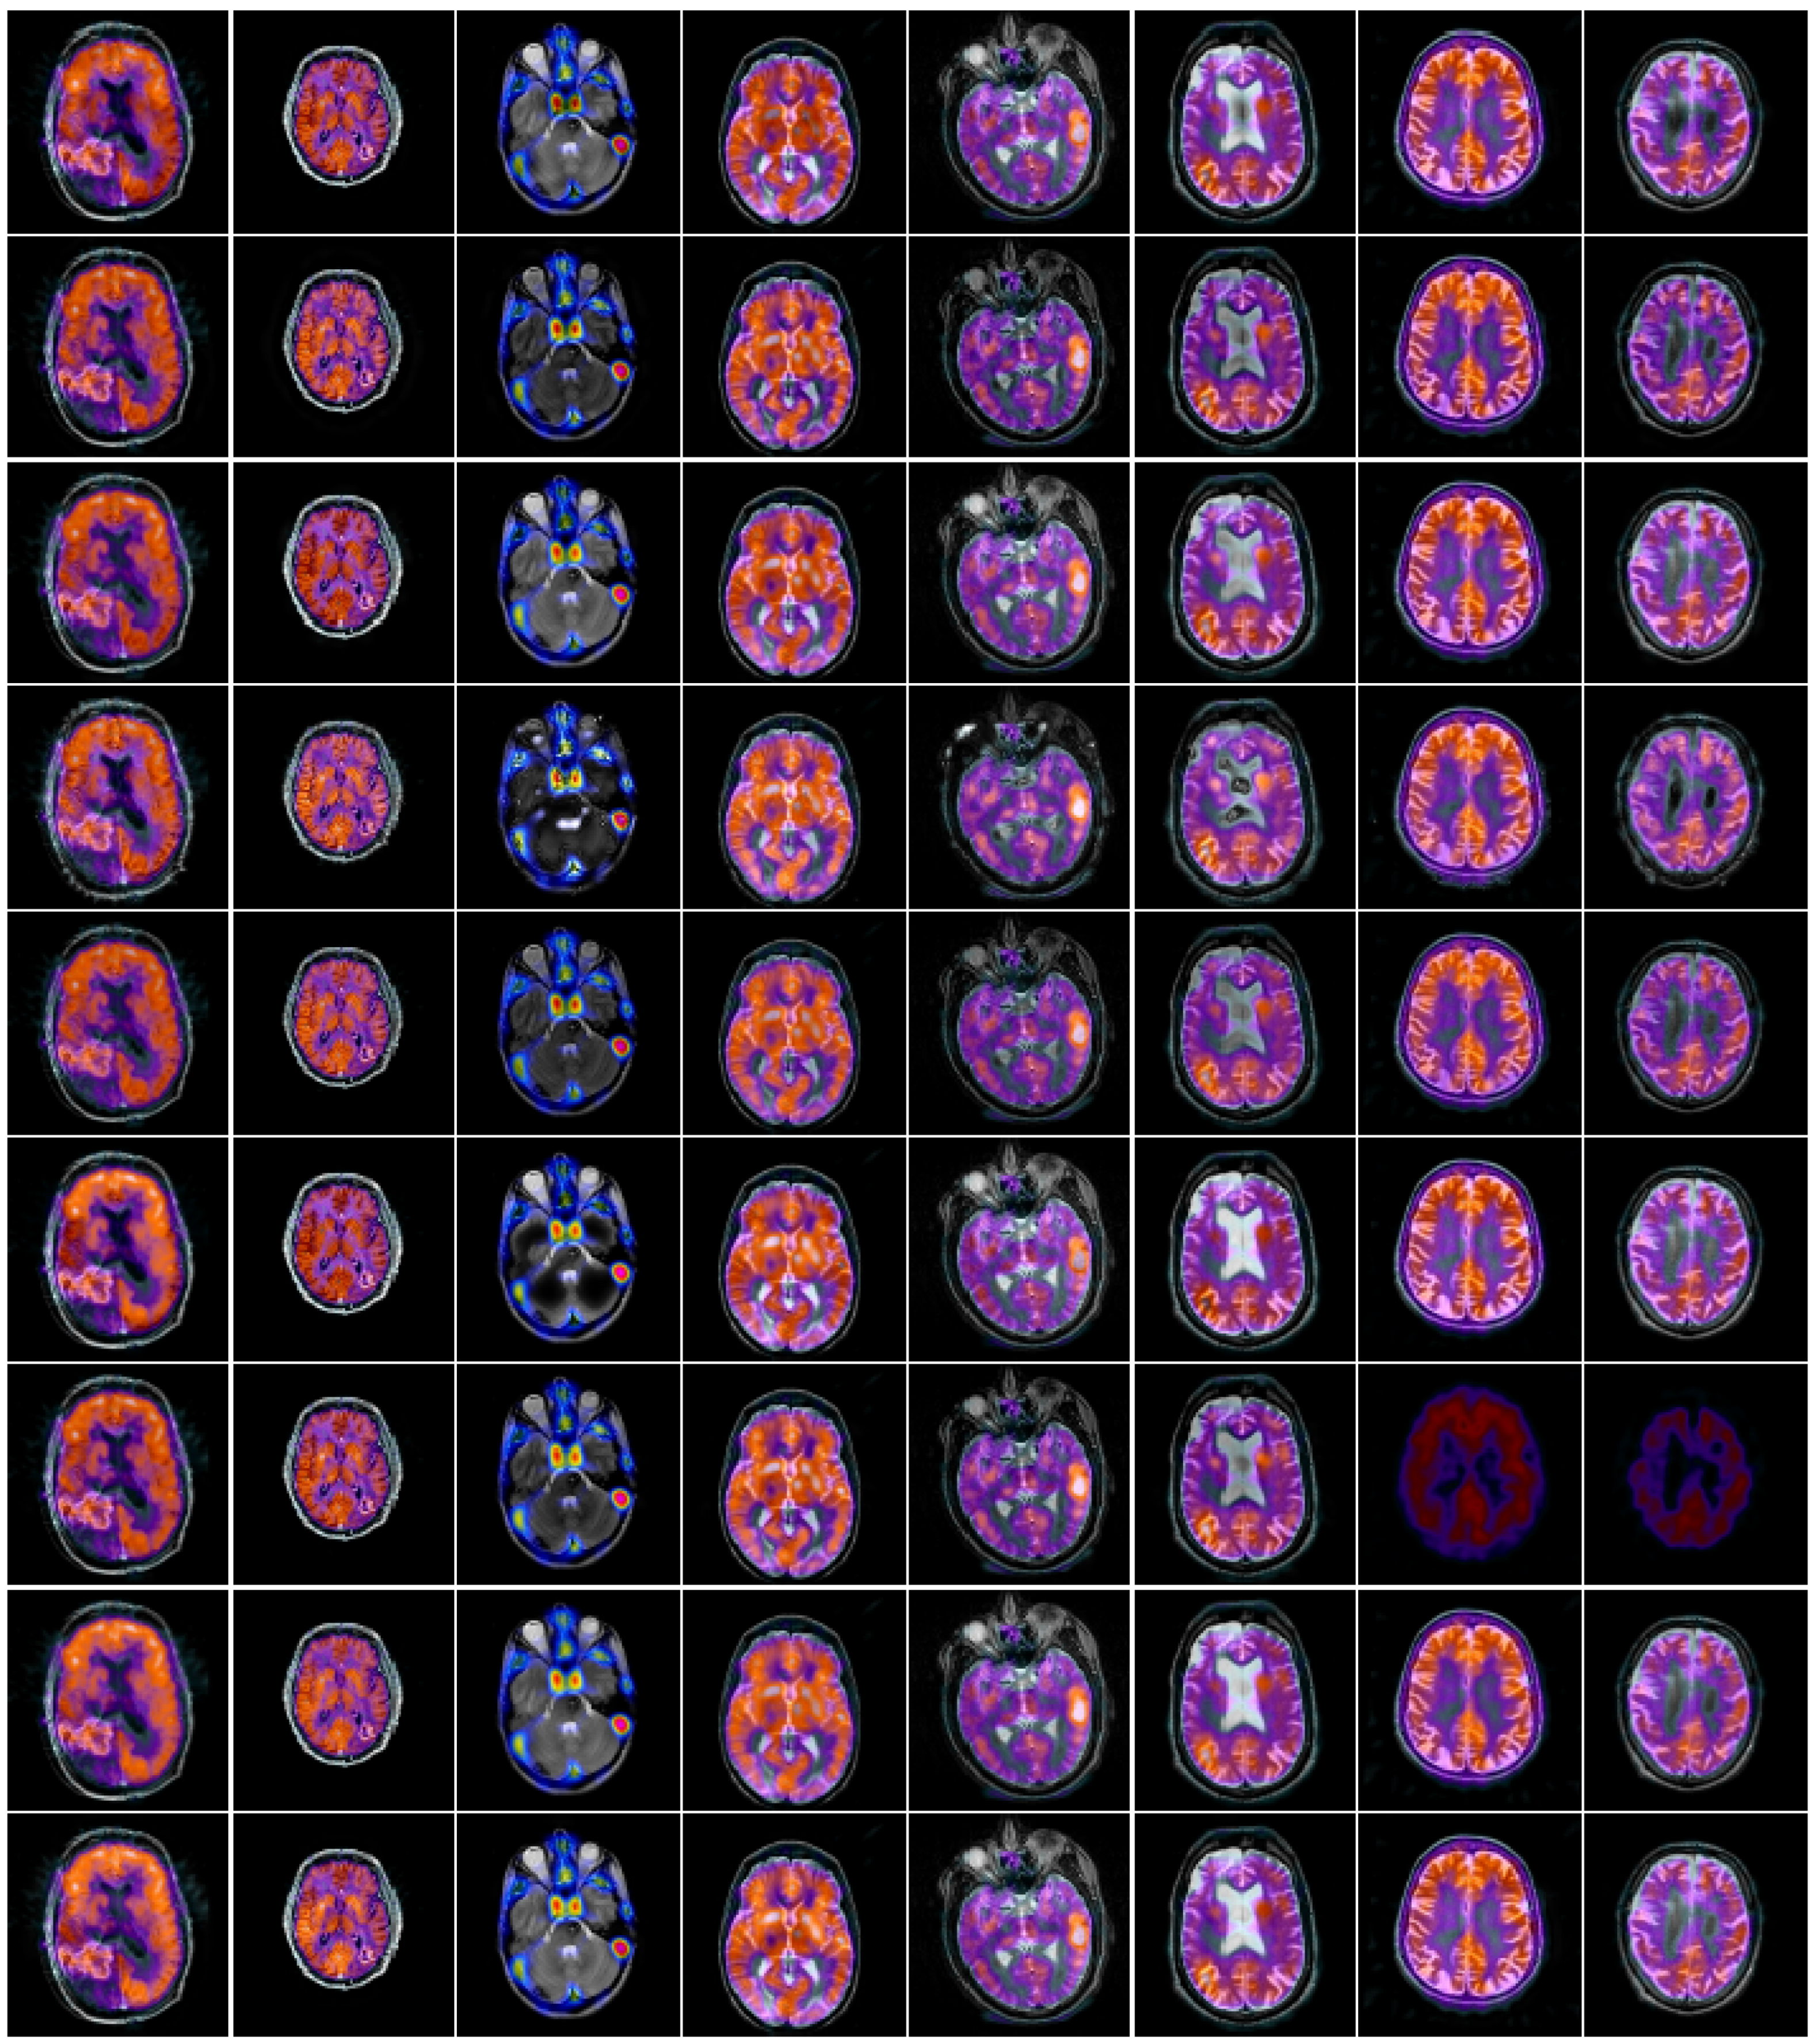

4.3. Comparison of Anatomical and Functional Image Fusion